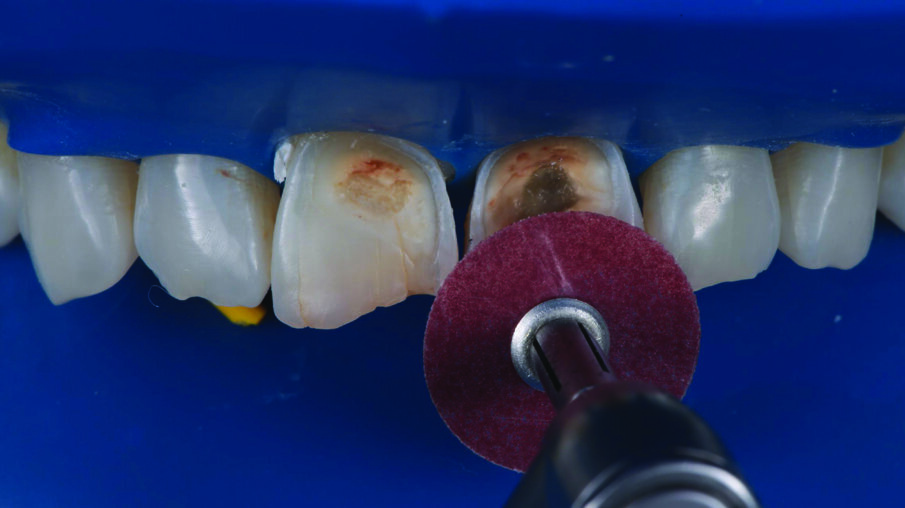

INITIAL SITUATION: Preoperative frontal view of the patient’s teeth, showing severe erosive tooth wear on the vestibular surfaces and incisal edges.

Detailed view of the maxillary incisors. The teeth didn’t show any highly translucent areas, so the use of a single shade/opacity of 3M™ Filtek™ Universal Restorative was selected.